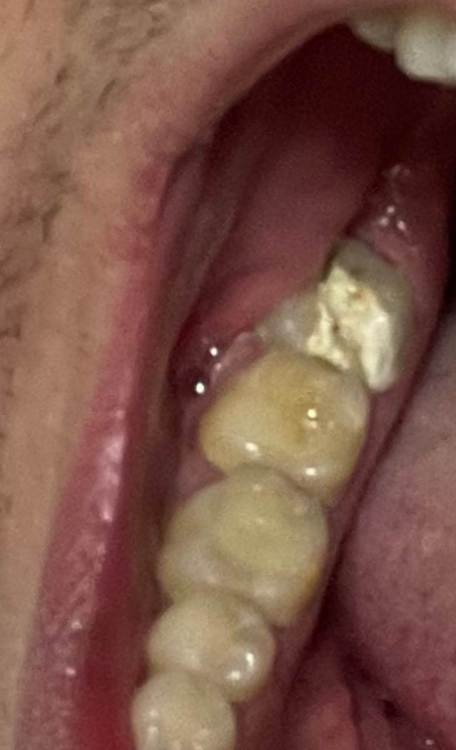

a.sataeff Опубликовано 10 июня, 2022 Поделиться Опубликовано 10 июня, 2022 (изменено) Добрый день. 35 лет. Можно ли спасти нижнюю восьмерку, разболелся, врач поставила пока лекарство. Стенки нет одной. Даже вопрос не можно, а нужно ли спасать? Изменено 10 июня, 2022 пользователем a.sataeff Ссылка на комментарий

red_butler Опубликовано 13 июня, 2022 Поделиться Опубликовано 13 июня, 2022 Здравствуйте, можно сохранить, но не рационально. Если он Вам дорог, то ищите грамотного терапевта для проведения лечения корневых каналов и востанавливайте зуб искусственной коронкой и меняйте подход к индивидуальной гигиене. А лучше прощайтесь с зубом 1 Ссылка на комментарий

red_butler Опубликовано 14 июня, 2022 Поделиться Опубликовано 14 июня, 2022 3 часа назад, a.sataeff сказал: Сходил очно в две клиники, в одной предложили штифт/пломба, в другой вкладку. в моём случае если удалять жалко, предпочтительнее коронка? Спасибо большое. Для полного понимания нужно оценить тот объем твердых тканей зуба который останется посте эндодонтического (корневых каналов) лечения, предварительно мне видится искуственная коронка. 1 Ссылка на комментарий